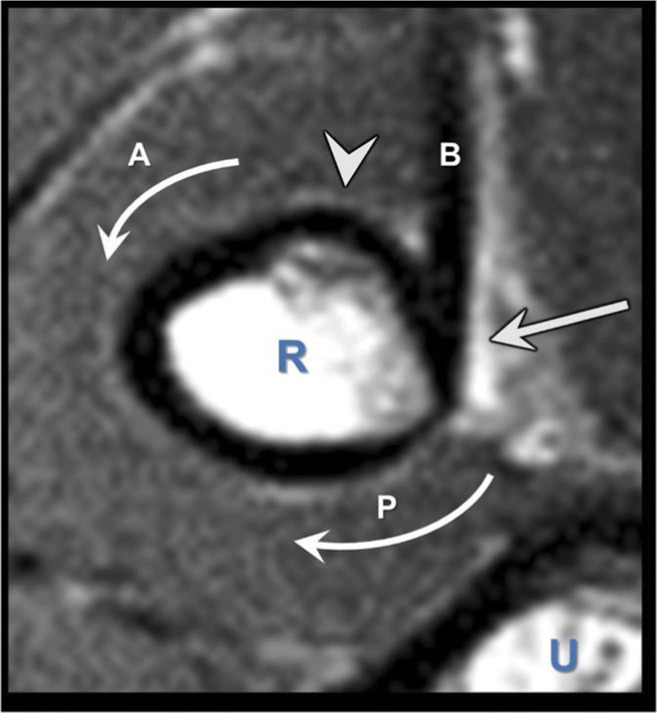

Figure 2.

The magnetic resonance imaging (MRI) axial view through the insertion of the distal biceps. The arrow shows the biceps tendon (B). The anterior (A) and posterior (P) curved arrows show the arc of the radial tuberosity. The protuberance (arrowhead) of the radial tuberosity is found anterior to the tendon insertion and is thought to function as a mechanical cam in increasing the supination moment of the biceps. R, radius; U, ulna. (Reprinted from J Bone and Joint Surgery, 2015, doi.org/10.2106/JBJS.N.01221, Schmidt CC, Brown BT, Williams BG, Rubright JH, Schmidt DL, Pic AC, Nakashian MR, Schimoler PJ, Miller MC with permission from Wolters Kluwer (The Importance of Preserving the Radial Tuberosity During Di... : JBJS (lww.com))

Two biomechanical studies have shown that an anterior reattachment site decreases supination torque by 15% in neutral and by 40% in 45° of supination (p=.01) and reduces supination moment arm by 27% in neutral and by 97% in 60° of supination (p<.05) [26, 29]. The protuberance at the radial tuberosity also plays a role in forearm supination as a cam (Fig. 2). Schmidt et al. [27] noted in their biomechanical study burring a socket/trough in the tuberosity results in a 27% loss (p=.04) in the biceps supination moment arm in a supinated forearm position. These mechanical studies imply that restoration of the insertional anatomy plays a significant role in restoration of pre-injury flexion and supination strength of the forearm. Only two clinical studies have looked at repair site location. Schmidt et al. [28] reported 19 patients who underwent distal biceps repair using an anterior approach. Post-operative MRI showed an insertion site angle of the repaired tendons was 73° more anterior than the uninjured controls (p<.001), and at 60° of forearm supination, supination strength was 67% of the uninjured side (p<.01) [28]. Another series of 27 patients underwent distal bicep repair via anterior approach; post-operative CT showed that the average suture anchor placement was 50° radial to the apex of the tuberosity [33]. Testing showed flexion strength of the repaired side was equal (97–106%) to that of the normal side, but supination strength (80–86%) and work (66–75%) performed were both weaker on the repaired side (66–75%; p<.05) [33]. In the contralateral side of the dominant arm of a non-athlete person, supination strength deficits may pass undetected. This may not be the case for athletes or laborers who require high level skills with the upper extremity. A clinical case is shown in Figure 3 emphasizing the importance of anatomic repair. This patient was a professional marksman who had difficulty stabilizing the gunstock of his rifle after anterior repair. After repair revision, patient was able to participate in his marksmanship.